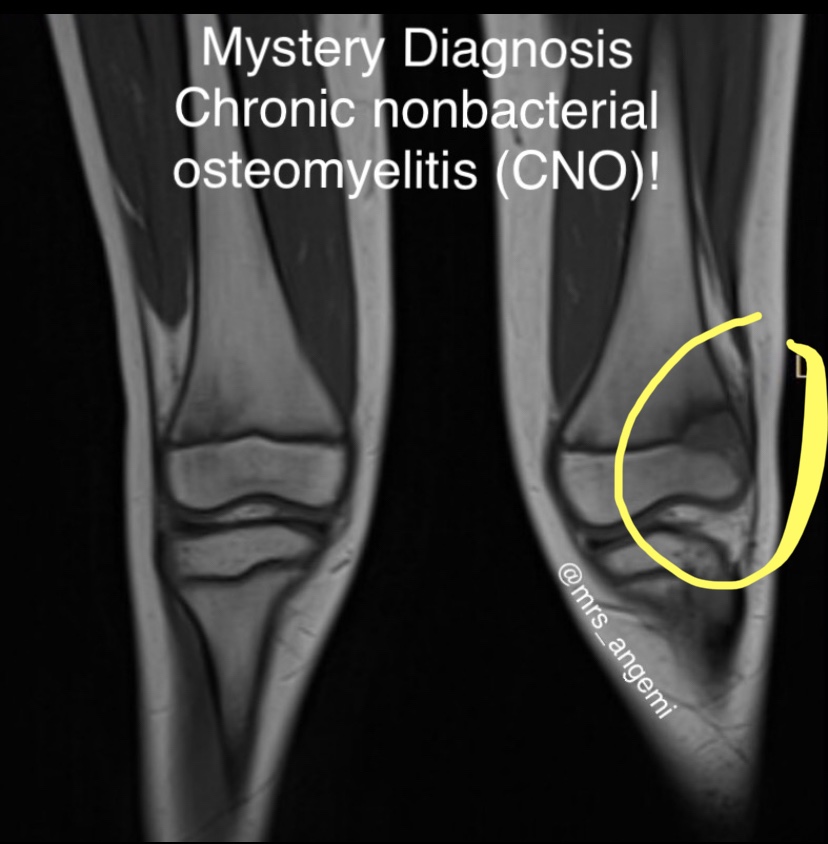

Mystery Diagnosis: Chronic Noninfectious Osteomyelitis! Gallery Mystery Diagnosis: Chronic Noninfectious Osteomyelitis! By Nicole Angemi|2024-09-11T16:32:23-04:00April 25th, 2022|The Gross Room, MEDICAL, Mystery Diagnosis, GAMES| Read More 10